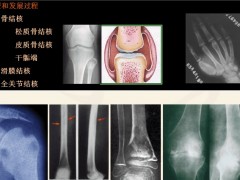

骨结核不是一种简单的疾病,这种疾病是身体其他地方发生病症而引发的,因此骨结核不是单独发生的,还会伴随其他的疾病,骨结核治疗起来也是很复杂的,需要长期的坚持用药和配合医生的治疗才有可能治好。